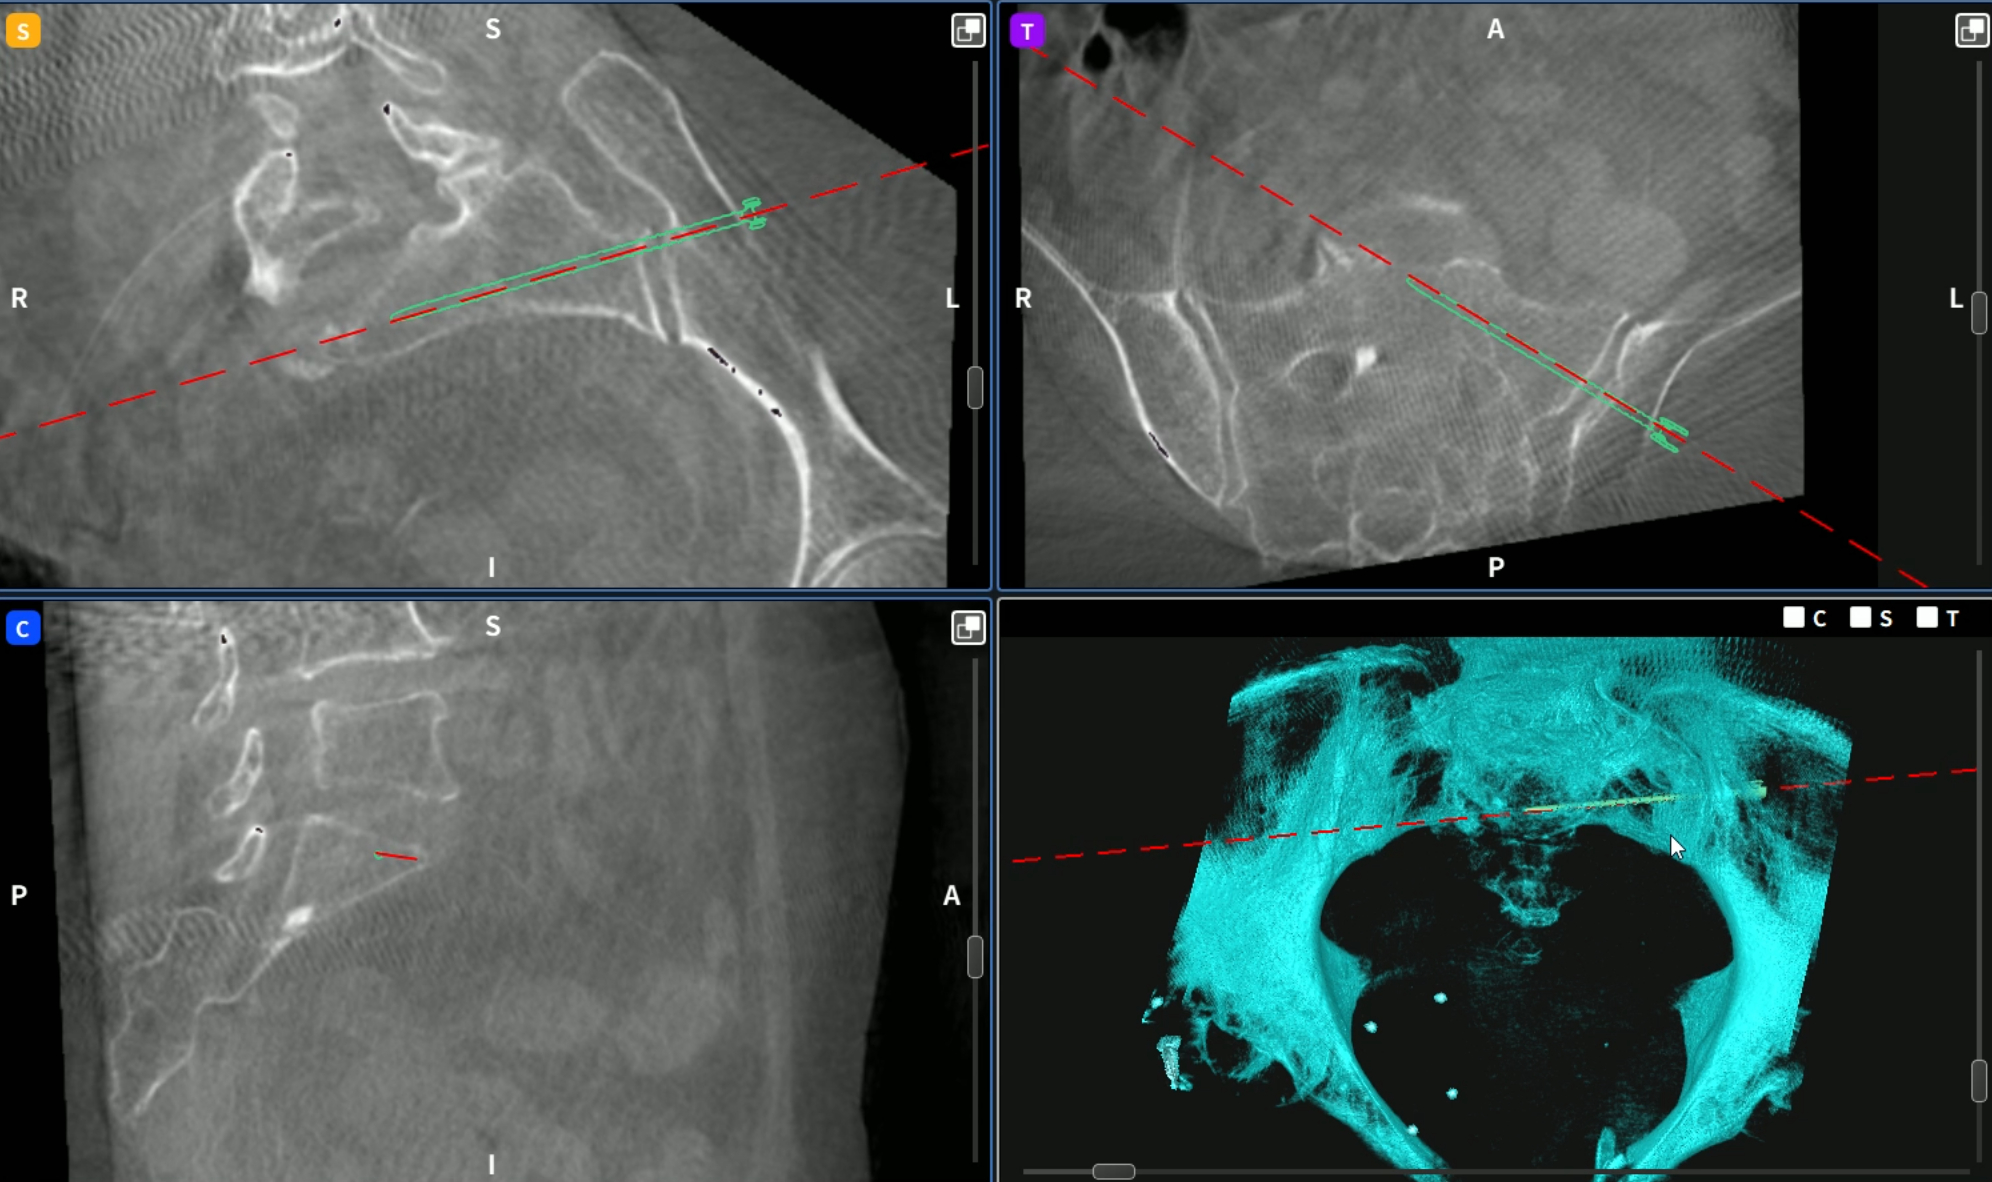

术中使用骨科手术机器人进行定位导航

术中使用骨科手术机器人导航定位置入骶髂螺钉